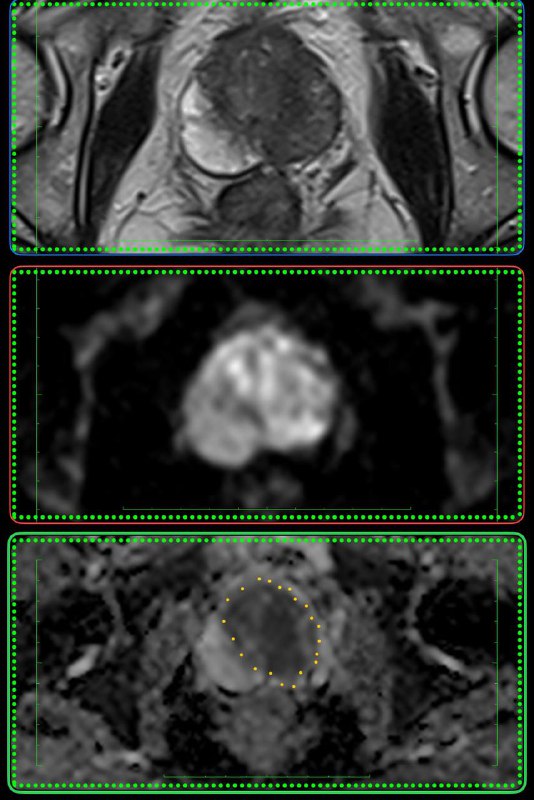

14 окт 2024

У пожилого мужчины после переохлаждения резко появилась задержка мочеиспускание, урологи утверждают, что у него – острый простатит. А на Магните – типичный рак, по крайней мере, PI-RADS 5.

Как считаете, может ли острый простатит выглядеть вот так? Асимметричный, с достаточно чётким контуром, да ещё и с быстрым накоплением контраста и быстрым же его вымыванием?

Что-то я сильно сомневаюсь, поделитесь опытом.

Когда рак простаты видно вот так, как здесь - исследование не вызывает отвращения, в отличие от случаев, когда приходится писать PIRADS-3..

Другое дело, что мы ж о пациентах заботимся, а не о себе, любимых, и каждый PIRADS-3 для пациента, все же, лучше, чем легко и непринуждённо обнаруживаемый, как в данном случае, PIRADS-5.

Пожелаем этому мужчине 75 лет успехов в лечении и минимума неприятных ощущений, которыми, неизбежно, такое лечение сопровождается.

Всем привет!

А вот для чего иногда нужен контраст на МРТ предстательной железы: по DWI, а она является основной последовательностью для оценки периферической зоны, типичные изменения ПИРАЦ-4 (наибольший размер - 12 мм), но вот на Т2 - жидкость, а не серость, и на постконтрастных накопления контраста нет вообще. Так что, это - абсцесс, а не рак.

Соблюдайте протокол и не будете разочарованы.